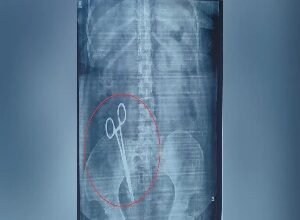

17 साल से महिला के पेट में थी कैंची, X-Ray हुआ तो उड़ गए होश; पति ने दर्ज कराई शिकायत

लखनऊ: यूपी की राजधानी लखनऊ से एक हैरान कर…